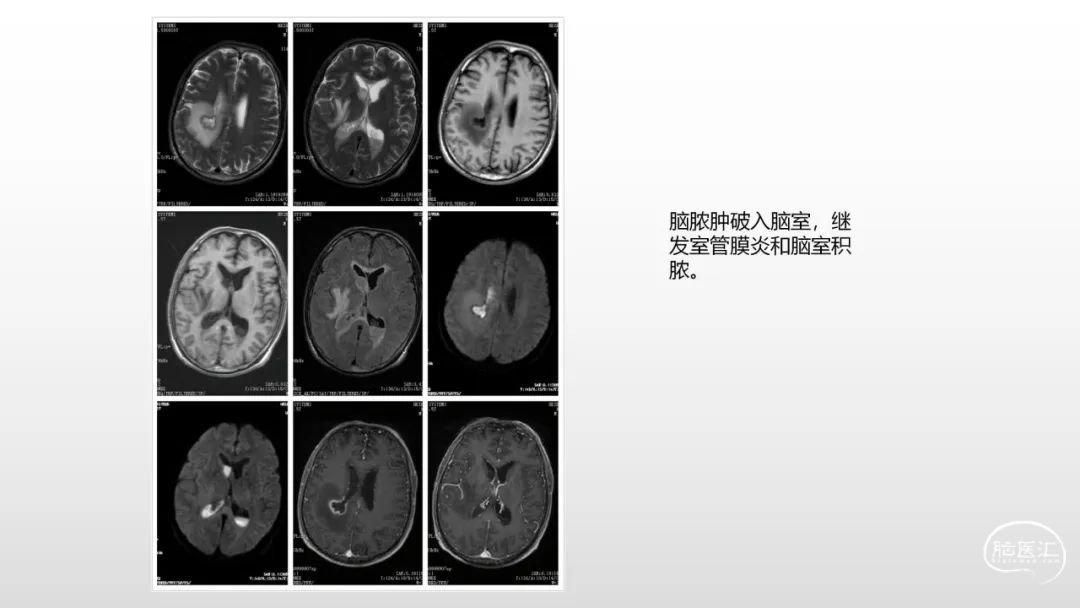

颅脑影像诊断基础知识讲座:感染和免疫性疾病1